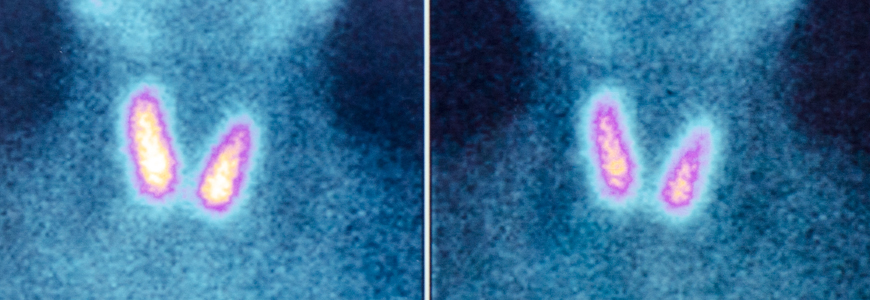

Lindsay Kenton Articles by Lindsay Kenton Pediatrics Life in the ‘Gray Zone’: Potentially Malignant Thyroid Nodule, Hyperthyroidism Requires Team Approach Ophthalmology Imaging Team Establishes Normative Optical Coherence Tomography Data for Children Ages 0-5 Neurology & Neurosurgery Stem Cell Transplantation for Multiple Sclerosis: Can Researchers Achieve A Cure? Urology Practice-Changing Advances for Men with Metastatic Prostate Cancer Interdisciplinary To Operate or Not To Operate for Adult Symptomatic Lumbar Scoliosis? Gastroenterology Advances in Esophageal Endoscopy Procedures Help Increase Options for Patients Ophthalmology New Neuro-Ophthalmology Division Chief Challenges Non-Surgical Perception of Profession Urology Duke-Led National Kidney Cancer Study Emphasizes Improving Overall Survival, Time Off Treatment Interdisciplinary Treating Neurocognitive, Physical Limitations in Patients with Brain Cancer Pediatrics Duke Expands Pediatric Clinical Services Based on Disease Rather Than Age Orthopaedics Total Joint Replacement Outpatient Surgery on the Rise Ophthalmology First-of-its-Kind Implant Shifts Glaucoma Treatment Landscape Pagination « First First page ‹ Previous Previous page 1 2 3 4 5 … Next › Next page Last » Last page